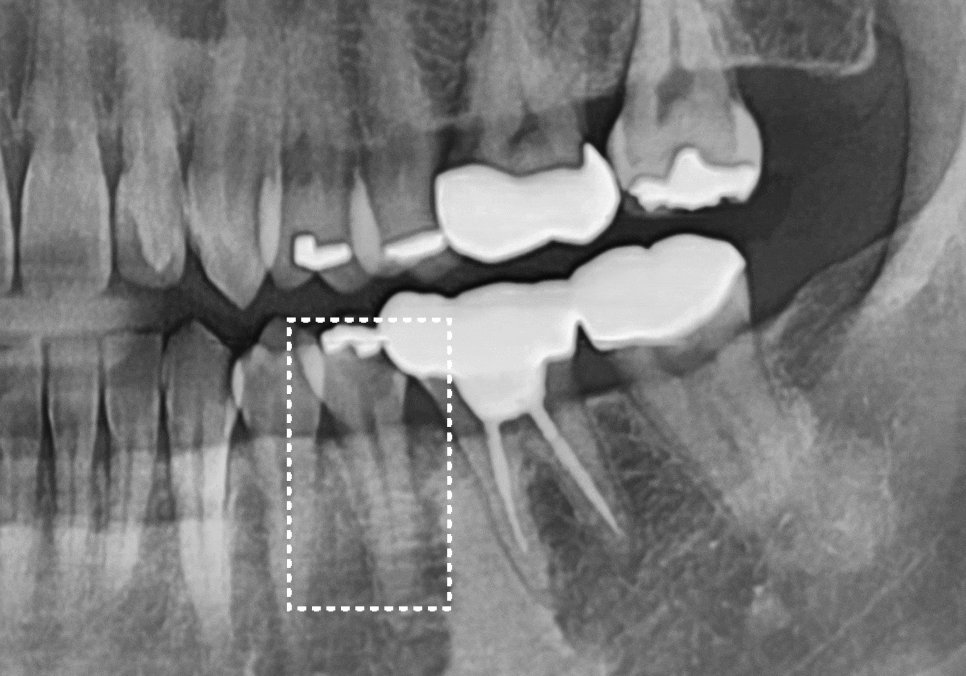

그로부터 5개월 뒤, 임플란트가 뼈와 단단하게

자리를 잡은 것을 확인하고

최종 보철 단계에 들어갔습니다.

임플란트는 오차 범위를 최소한으로 줄여서,

정확한 보철물을 만드는 것이 무엇보다 중요한데요.

저희는 구강 스캐너를 통해 입안 구조를

디지털 데이터로 정밀하게 채득하기 때문에,

고무 재료로 본을 뜰 때 생길 수 있는

미세한 변형을 최소화하고 있습니다.

이렇게 얻은 정교한 데이터를 바탕으로

원내 기공소에서 환자분만을 위한

맞춤형 보철물을 제작했습니다.

251121

제가 직접 확인하며 주변 치아와 잘 맞물리도록

세밀하게 조정해 드렸고,

이제는 환자분도 예전처럼

편안하게 식사하고 계십니다. ^^